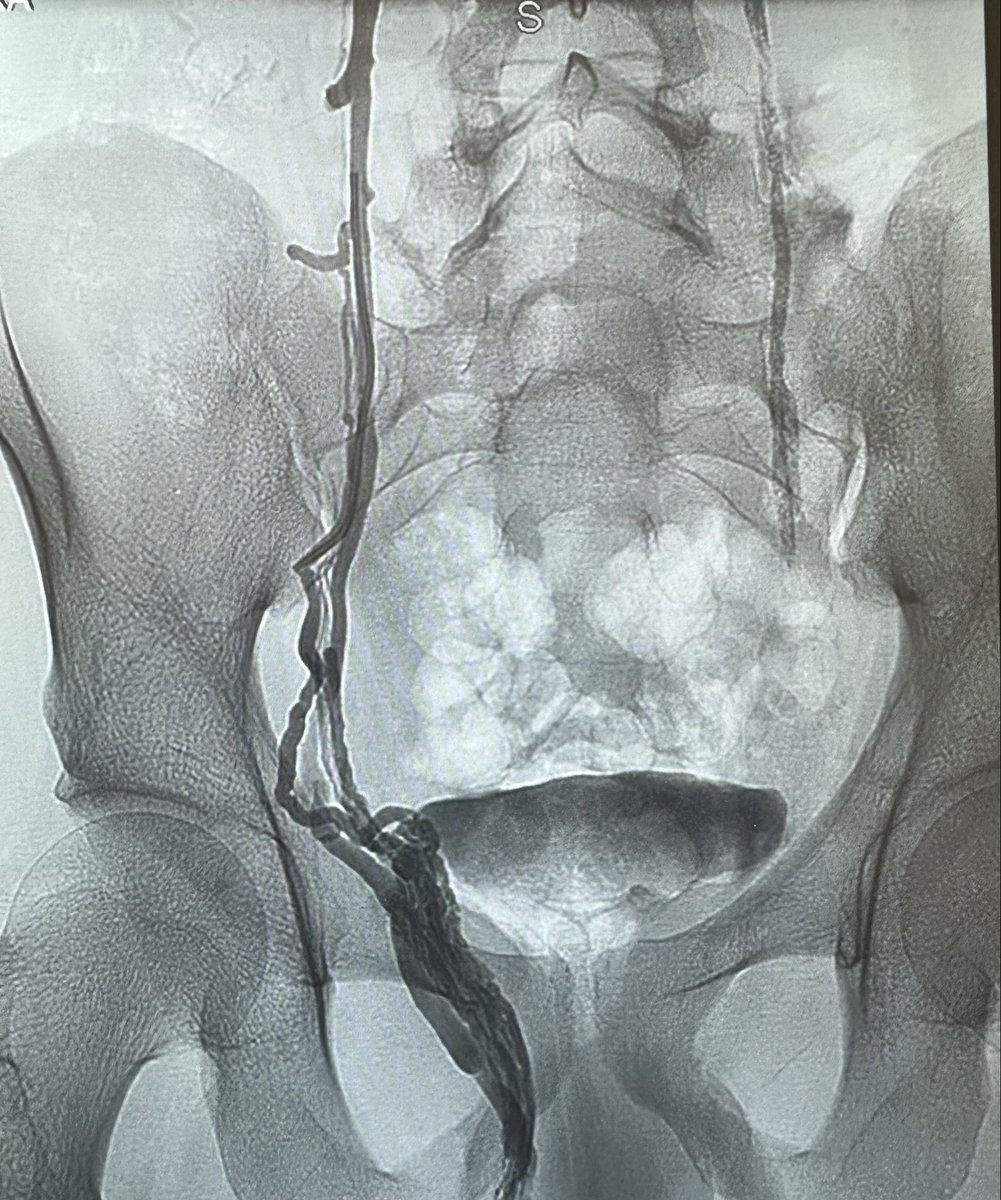

علاج دوالي الخصية بالأشعة التداخلية ، العلاج بالصمغ الطبي يعتبر أفضل وأحدث علاج. يتم إغلاق الدوالي والأوردة بدقة دون التعرض للشرايين والقنوات الليمفاوية الدقيقة. مثال لمريض لديه ما يفوق عن ٤٠ وريد ، لا يمكن ربطها جميعاً جراحياً. بالقسطرة؟ انتهينا من الجهتين خلال اقل من ١٠ دقائق.

من النوادر أن تكون دوالي الخصية اليمين أكبر من اليسار. بالقسطرة ، يمكن الكشف وعلاج الجهتين بسهولة عن طريق قسطرة واحدة باليد (فتحة لا تتجاوز ٢ مم) ويمكن علاج كل الدوالي حتى الصغيرة. ماذا عن الجراحة؟ يحتاج الجراح لعمل شق جراحي (٢-٣ سم) في كل جهة وفقط يمكنه ربط الدوالي الكبيرة…